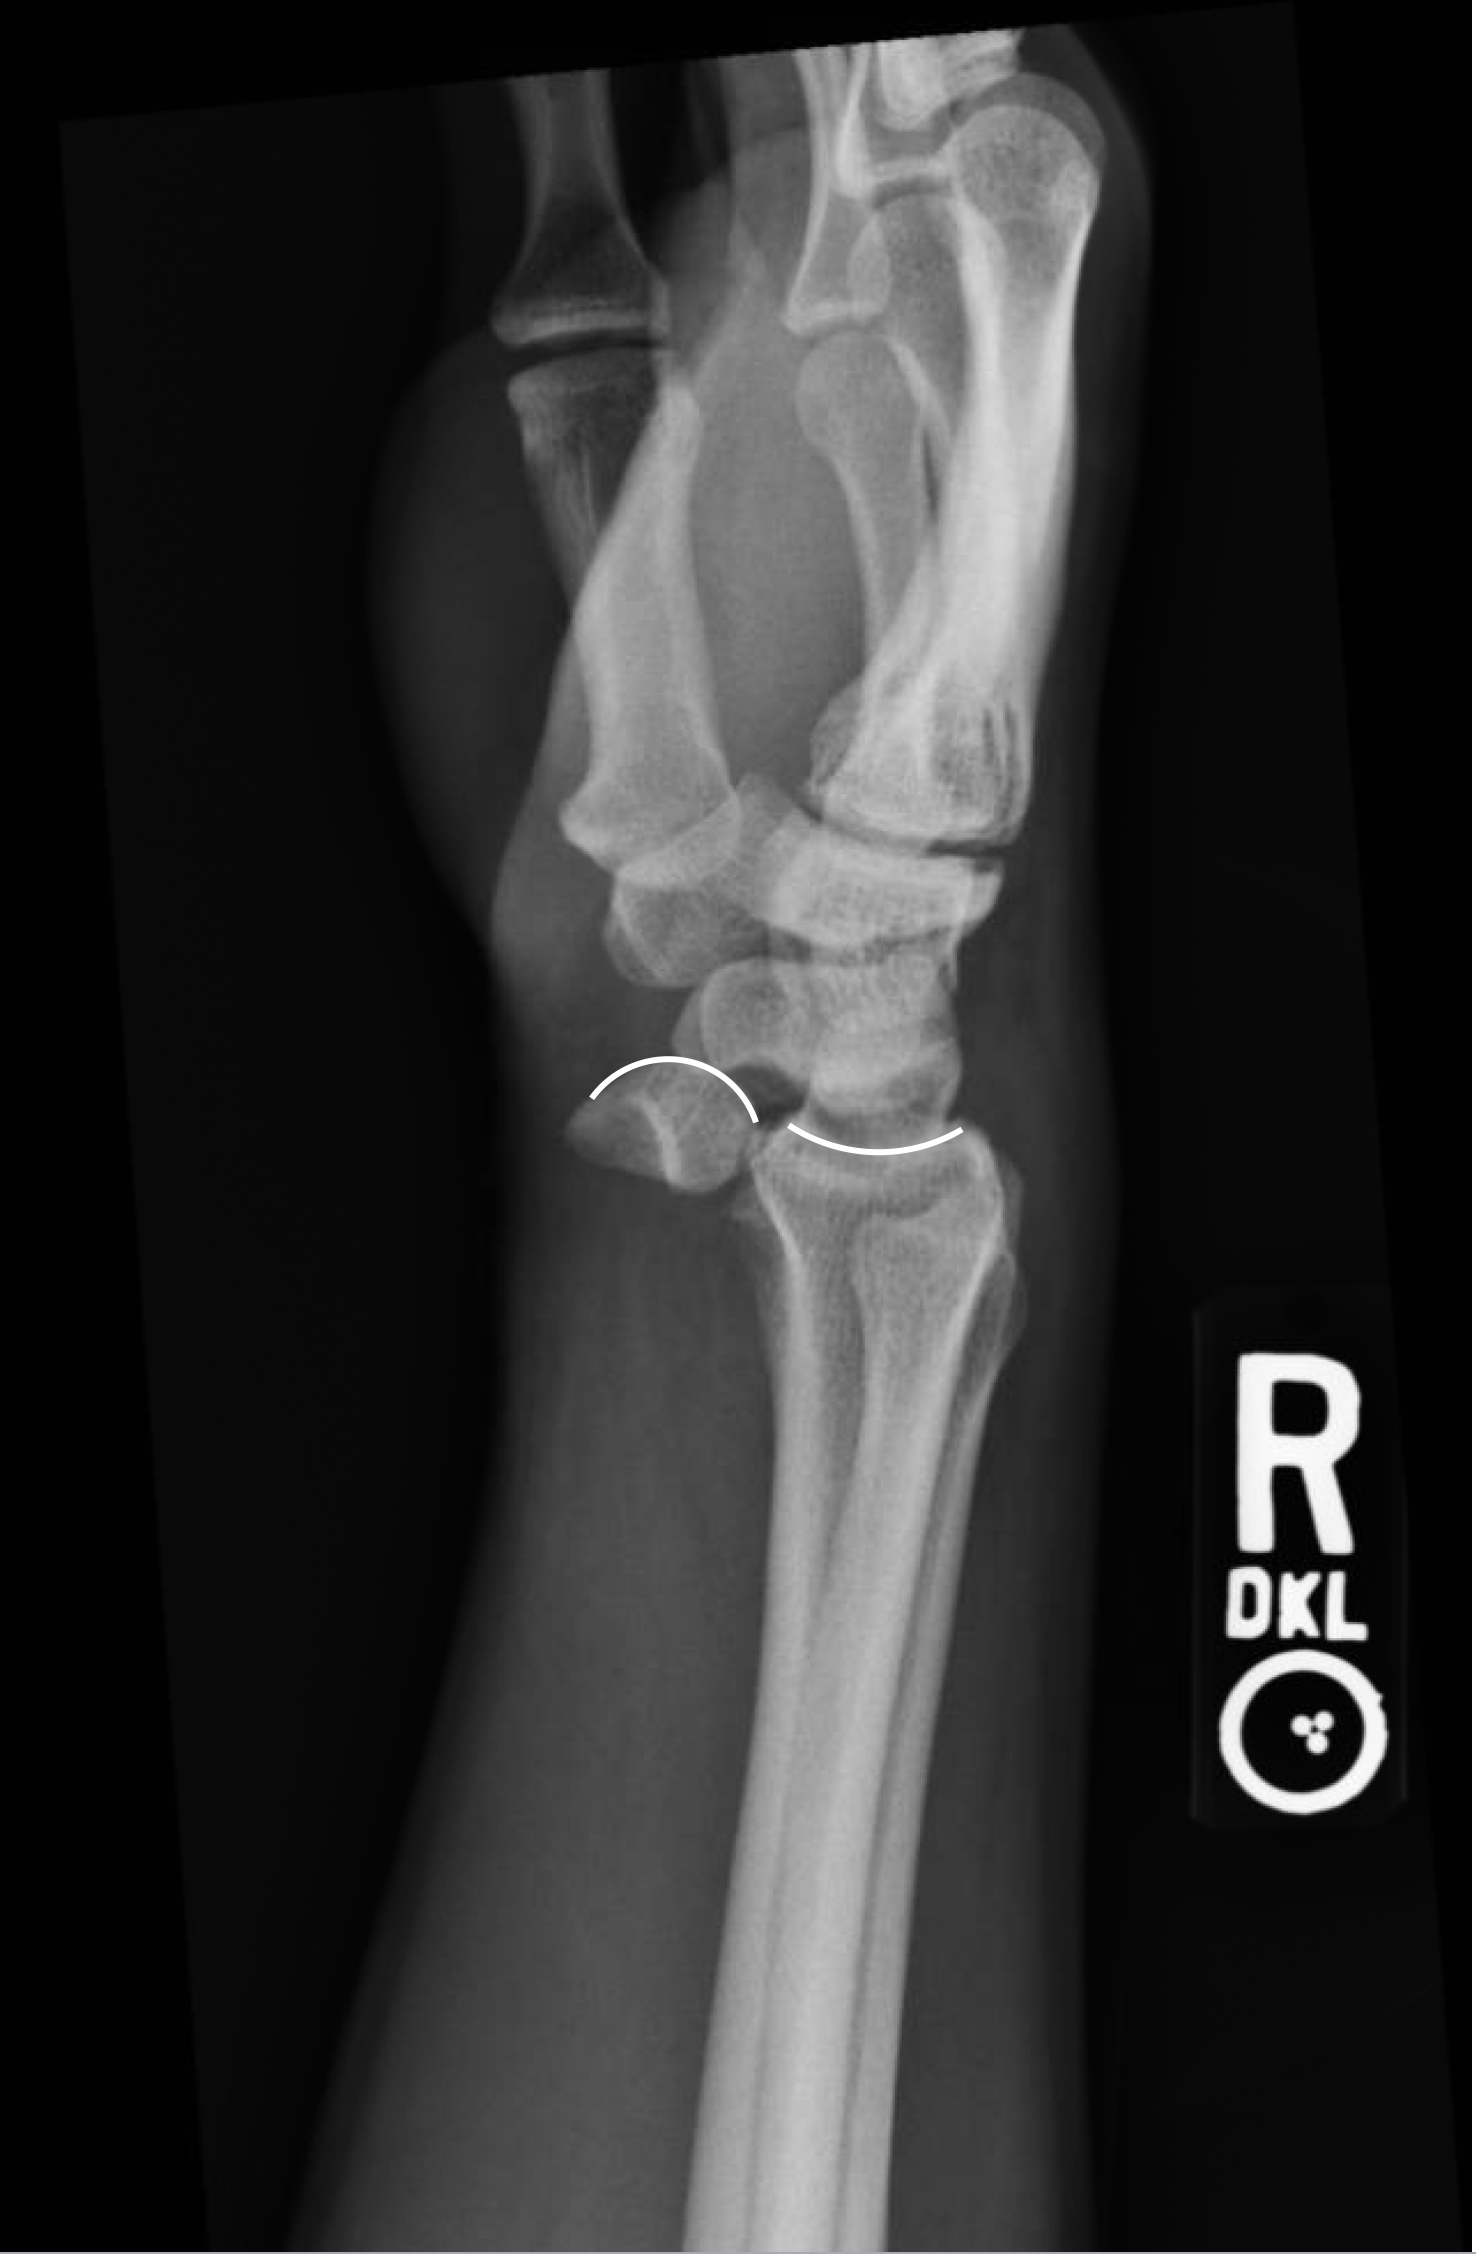

Lunate dislocation Radiology at St. Vincent's University Hospital What Is Sclerosis Of Lunate Bone Diagnosis can be made with. Kienbock's disease is the avascular necrosis of the lunate which can lead to progressive wrist pain and abnormal carpal motion. If you’ve been diagnosed with. Subchondral sclerosis is a thickening of bone that happens in joints affected by osteoarthritis. The lunate bone begins to harden due to the lack of blood supply during stage ii.. What Is Sclerosis Of Lunate Bone.

Lunate Dislocation What Is Sclerosis Of Lunate Bone Kienböck’s disease, is a rare, debilitating condition that can lead to chronic pain and dysfunction. It happens when one of the eight small. The cutoff of blood to your lunate makes the bone harden. The lunate bone begins to harden due to the lack of blood supply during stage ii. Your wrist may be swollen, tender, and painful. If you’ve. What Is Sclerosis Of Lunate Bone.

Lunate dislocation Image What Is Sclerosis Of Lunate Bone Diagnosis can be made with. Kienbock's disease is the avascular necrosis of the lunate which can lead to progressive wrist pain and abnormal carpal motion. This hardening process is called sclerosis and is an abnormal increase in bone density. Your wrist may be swollen, tender, and painful. Subchondral sclerosis is a thickening of bone that happens in joints affected by. What Is Sclerosis Of Lunate Bone.

Lunate Dislocation JETem What Is Sclerosis Of Lunate Bone The lunate bone begins to harden due to the lack of blood supply during stage ii. Kienbock's disease is the avascular necrosis of the lunate which can lead to progressive wrist pain and abnormal carpal motion. If you’ve been diagnosed with. It happens when one of the eight small. Kienböck’s disease is the eponym for avascular necrosis of the lunate. What Is Sclerosis Of Lunate Bone.